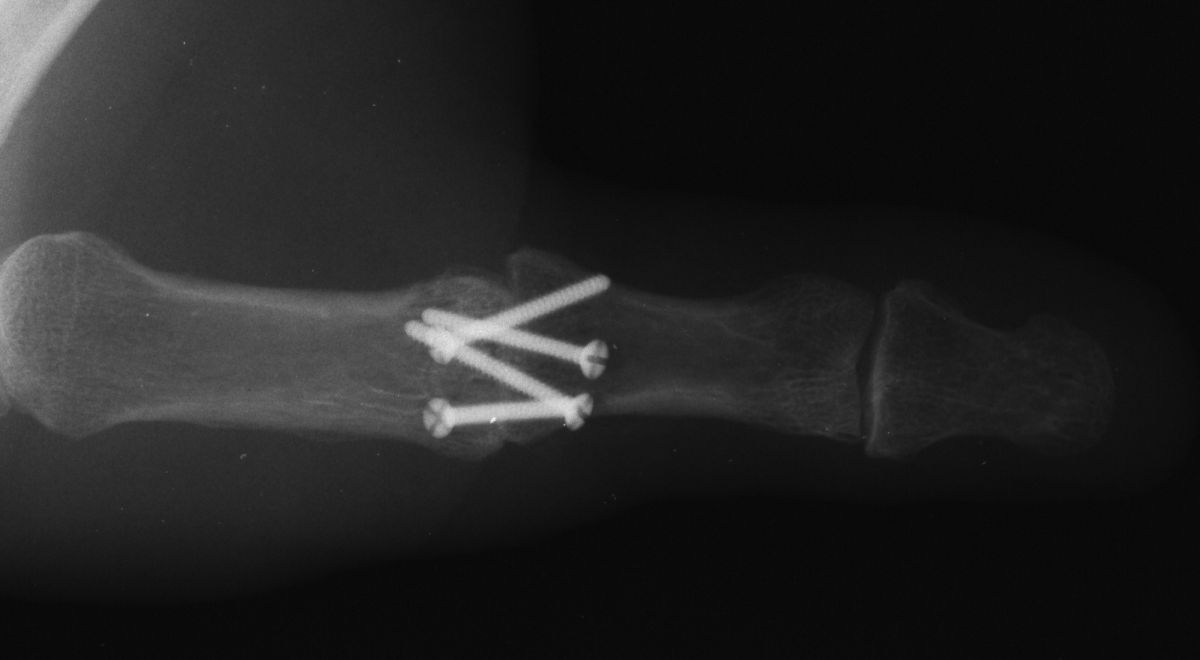

| Smaller plates and screws

from the Lorenz craniofacial fixation system were used for this MCP

fusion. |

| Low profile, but possibly

too small in terms of rigidity. Despite this concern, the patient did

well. |